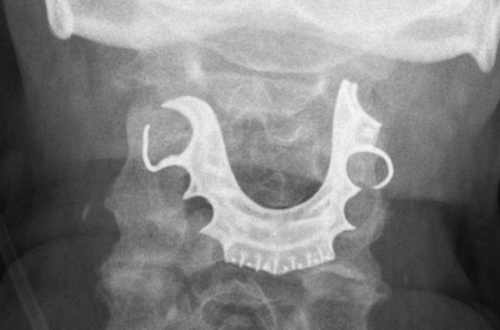

Dois dias depois, ele retornou à unidade. Foi quando a equipe médica encontrou um objeto semicircular sobre as cordas vocais do idoso. O paciente contou aos médicos que perdeu sua dentadura durante o tempo que ficou no hospital.